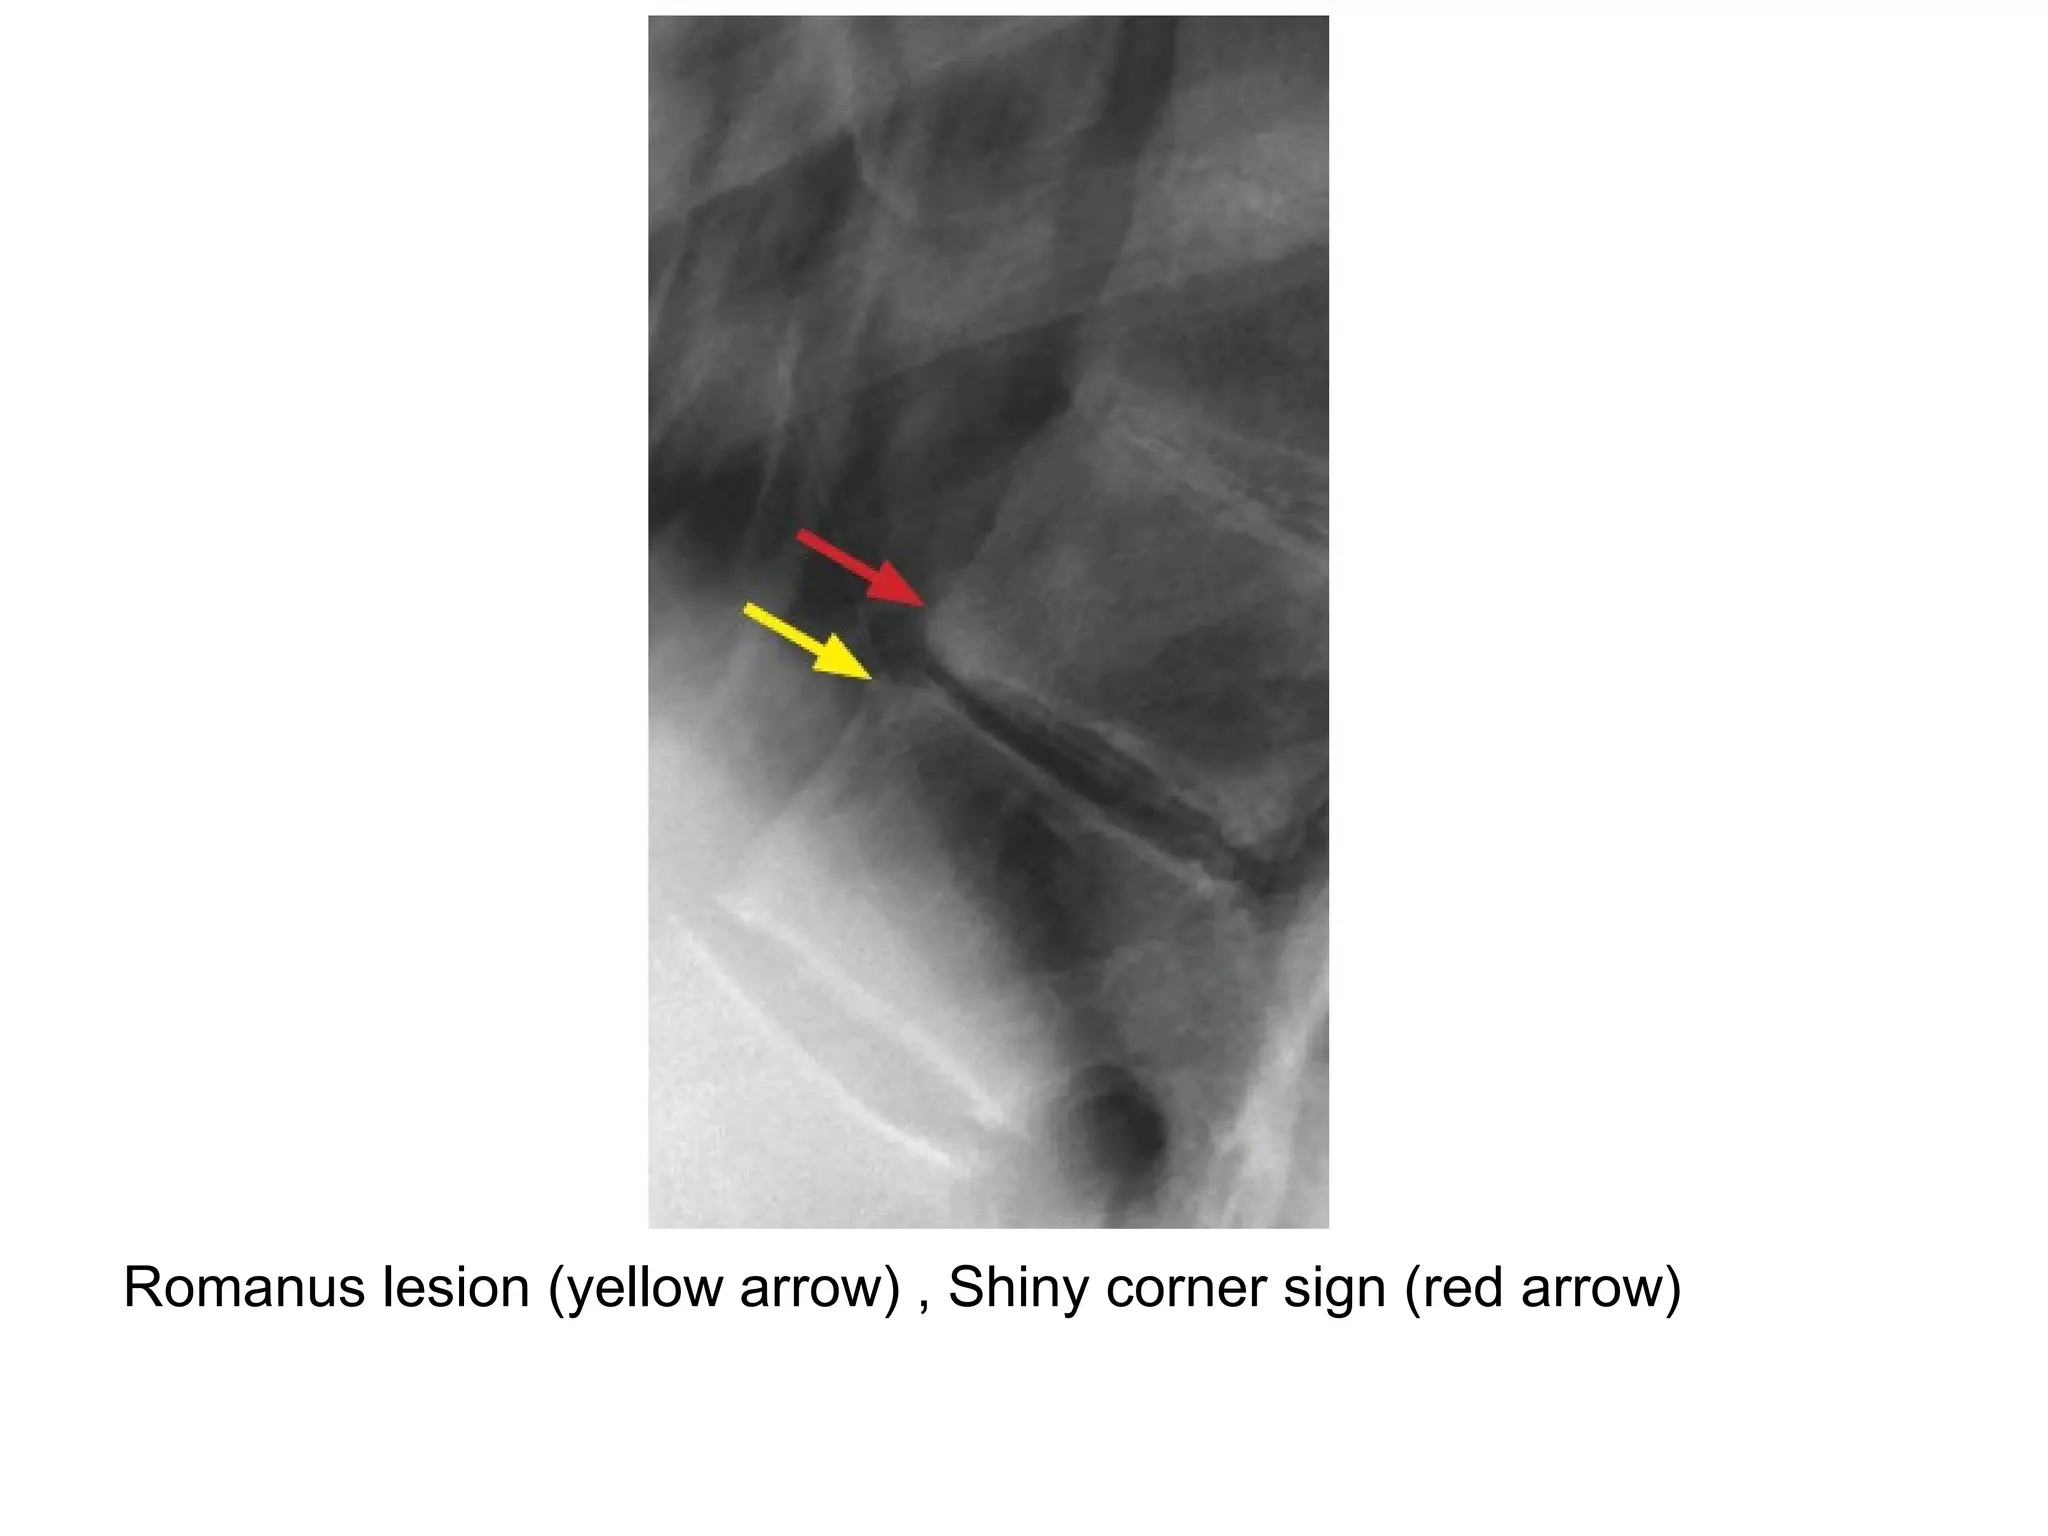

1-Shiny corner sign :

-Represents small erosions at the superior and

inferior endplates (corners on lateral radiograph)

of the vertebral bodies with surrounding reactive

sclerosis , Romanus lesions are erosions wjile

shiny corners are sclerosis of prior Romanus

lesions at the corner of the body

Romanus lesion (yellow arrow) , Shiny corner sign (red arrow)